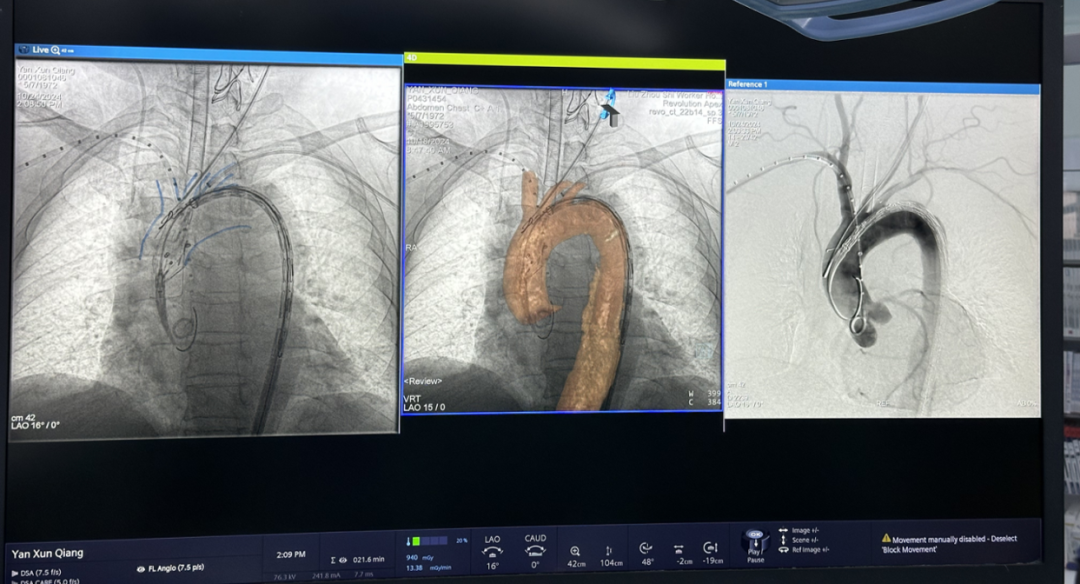

术中3D影像引导,主体支架精准定位

3D影像引导下,

主体支架窗口与弓上三分支开口对位

依次超选无名、左颈总及左锁骨下动脉

术后造影,支架形态良好,分支血流通畅